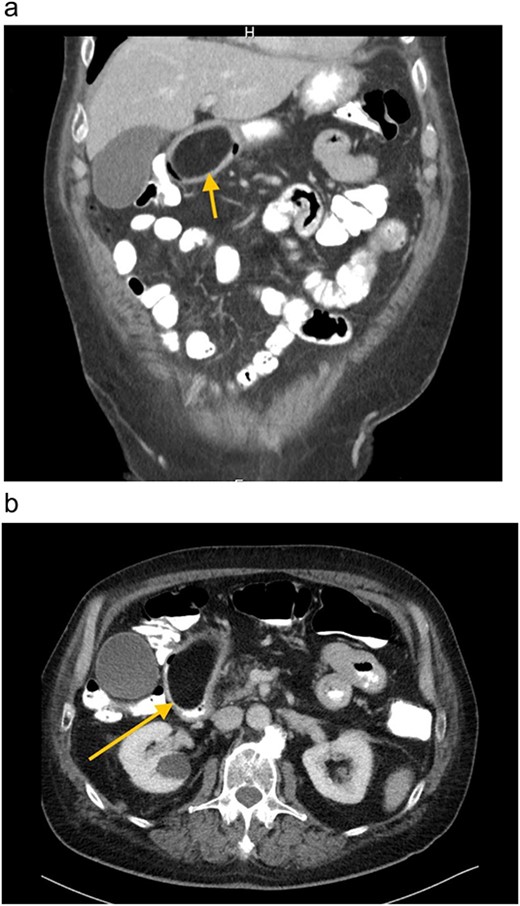

A 67-year-old white German man with a known history of fully treated rectal cancer in 2011 presented with weight loss (13 kg in 3 months), night sweats, constipation and a feeling of fullness after small meals. Liquid diet was well tolerated. A computer tomography (CT) scan done 4 months prior to the presentation showed an incidentally discovered duodenal mass ⁓7.4 × 4.4 cm pressing the Pylorus without signs of inflammation or lymphadenopathy (Fig. 1). All related laboratory values were within the normal range. Subsequent endoscopic gastroscopy demonstrated Pylorus compression with a lipoma-like structure in the first part of the Duodenum. Due to the large size of the mass and the risk of bleeding, as well as the limited endoscopic access to the mass, robotic-assisted duodenotomy was performed as the treatment (Fig. 2). Histology revealed a benign lipomatous tissue, which was successfully removed via surgical excision. Postoperative follow-ups revealed a marked improvement in the patient's symptoms, along with a notable weight gain.

(a) and (b) CT-Abdomen, showing duodenal mass ⁓7.4 × 4.4 cm pressing the Pylorus.